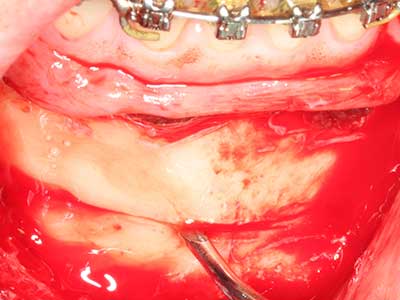

La piezochirurgia presenta altri vantaggi per quanto riguarda la raccolta di blocchi ossei. Oltre all'elevata precisione dell'osteotomia appena descritta, l'utilizzo di puntine per sega molto sottili permette di minimizzare in maniera significativa la perdita di materiale. È molto probabile che si verifichi una maggiore perdita di materiale durante la raccolta utilizzando puntine di strumenti più spessi, in particolare delle frese Lindemann (Lakshmiganthan, Gokulanathan et al. 2012). La separazione basale, necessaria in particolare per i trapianti di blocchi nella zona retromolare, viene semplificata grazie a seghe specificatamente progettate di forma rettangolare; di conseguenza la piezochirurgia è considerata una procedura precisa, semplice e sicura per la raccolta di blocchi di osso nella zona retromolare (Happe 2007) (figg. 1-12).

Il tessuto osseo non è semplicemente una struttura minerale, ma contiene anche una percentuale significativa di fibre di collagene. Ciò significa che non possiede solo una buona forza di compressione, ma anche un certo livello di flessibilità che è possibile sfruttare durante l'esecuzione degli accrescimenti di osso. Nella procedura di espansione classica con incisione ossea, la cresta alveolare atrofizzata viene incisa longitudinalmente ed espansa con cautela dopo aver raggiunto una profondità di osteotomia adeguata (figg. 13-16), idealmente senza una sostanziale rimozione del periostio (Brugnami, Caiazzo et al. 2014, Stricker, Fleiner et al. 2014). I sistemi a piastra e vite con distanza di espansione incrementale si sono dimostrati efficaci nella separazione delle due lamelle ossee restando al di sotto della soglia di frattura. In generale, sono richieste larghezze dell'osso residuo di almeno 3-4 mm (Chiapasco, Zaniboni et al. 2006) per garantire un'adeguata flessibilità e una copertura sufficiente dell'osso per gli impianti futuri. Se necessario, un'osteotomia di rilascio verticale su uno o più lati può migliorare la flessibilità. Una combinazione con ulteriori tecniche di accrescimento, in particolare dal lato buccale, è stata descritta come un'alternativa alla tecnica classica.